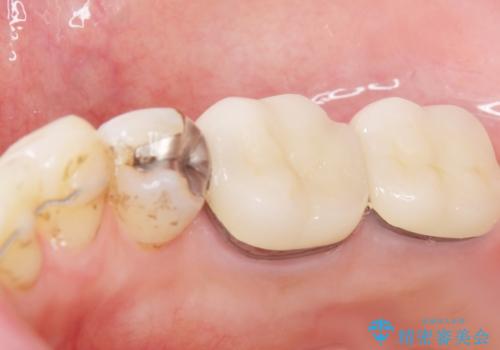

低予算で銀歯を白くしたい 50代女性

- 低予算で銀歯を白くしたいとご希望し来院された患者様です。

右上小臼歯(右上5)はオールセラミッククラウン(e-max press)、下顎臼歯(下顎両側67)はメタルボンドクラウンによりやりかえることにしました。

銀歯がなくなったとことで口元の印象が明るくなり、ご満足頂けました。

「これで大きく口を開けて笑っても大丈夫だわ!」と喜んで下さいました。

~クラウンの種類~

右上小臼歯(右上5):オールセラミッククラウン エコノミー

下顎両側臼歯(下顎両側67):メタルボンドクラウン エコノミー